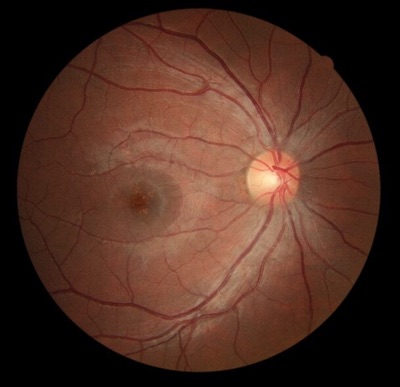

OD Fundus

OCT Macula Over a decade of partnership with the eye care community. Preserving 25+ years of clinical history.